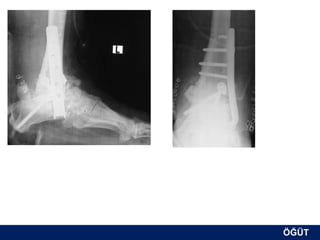

OLGU No 3

FK, 58y, ♂

Erken postop

ÖĞÜT

6.ay